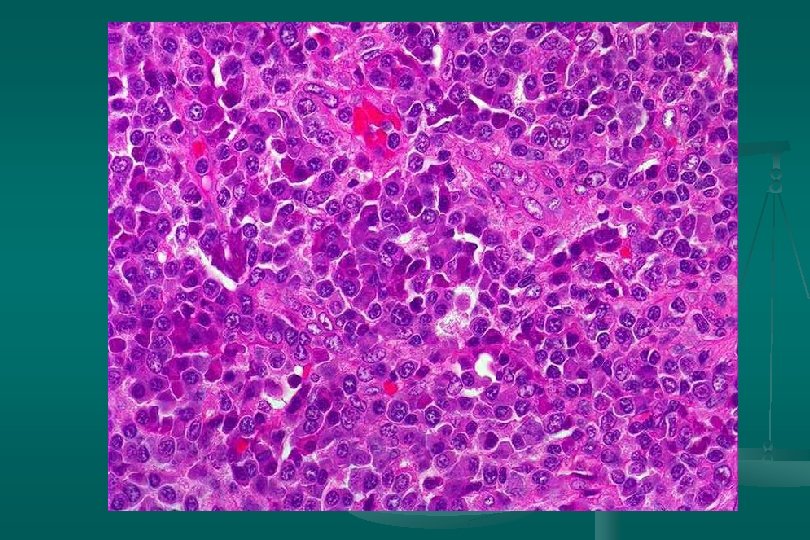

Enfermedad de Castleman Histología: dos categorías: 1. Tipo vascular hialino (angiofolicular): n Folículos grandes, proliferación vascular y hialinización central. n Capas concéntricas de linfocitos en la periferia del folículo (capas de cebolla). n Estroma interfolicular: prominente, venulas poscapilares hiperplásicas, CP, E. inmunoblastos n

Enfermedad de Castleman Subtipo linfoide: *Expansión zona del manto *Centros germinales pequeños. 2. Tipo células plasmáticas: n Proliferación difusa de cels plasm interfolicular + cuerpos de Russell n Cambio vascular-hialino: ausente n Depósito de material acidofílico amorfo (fibrina y complejos inmunes) n